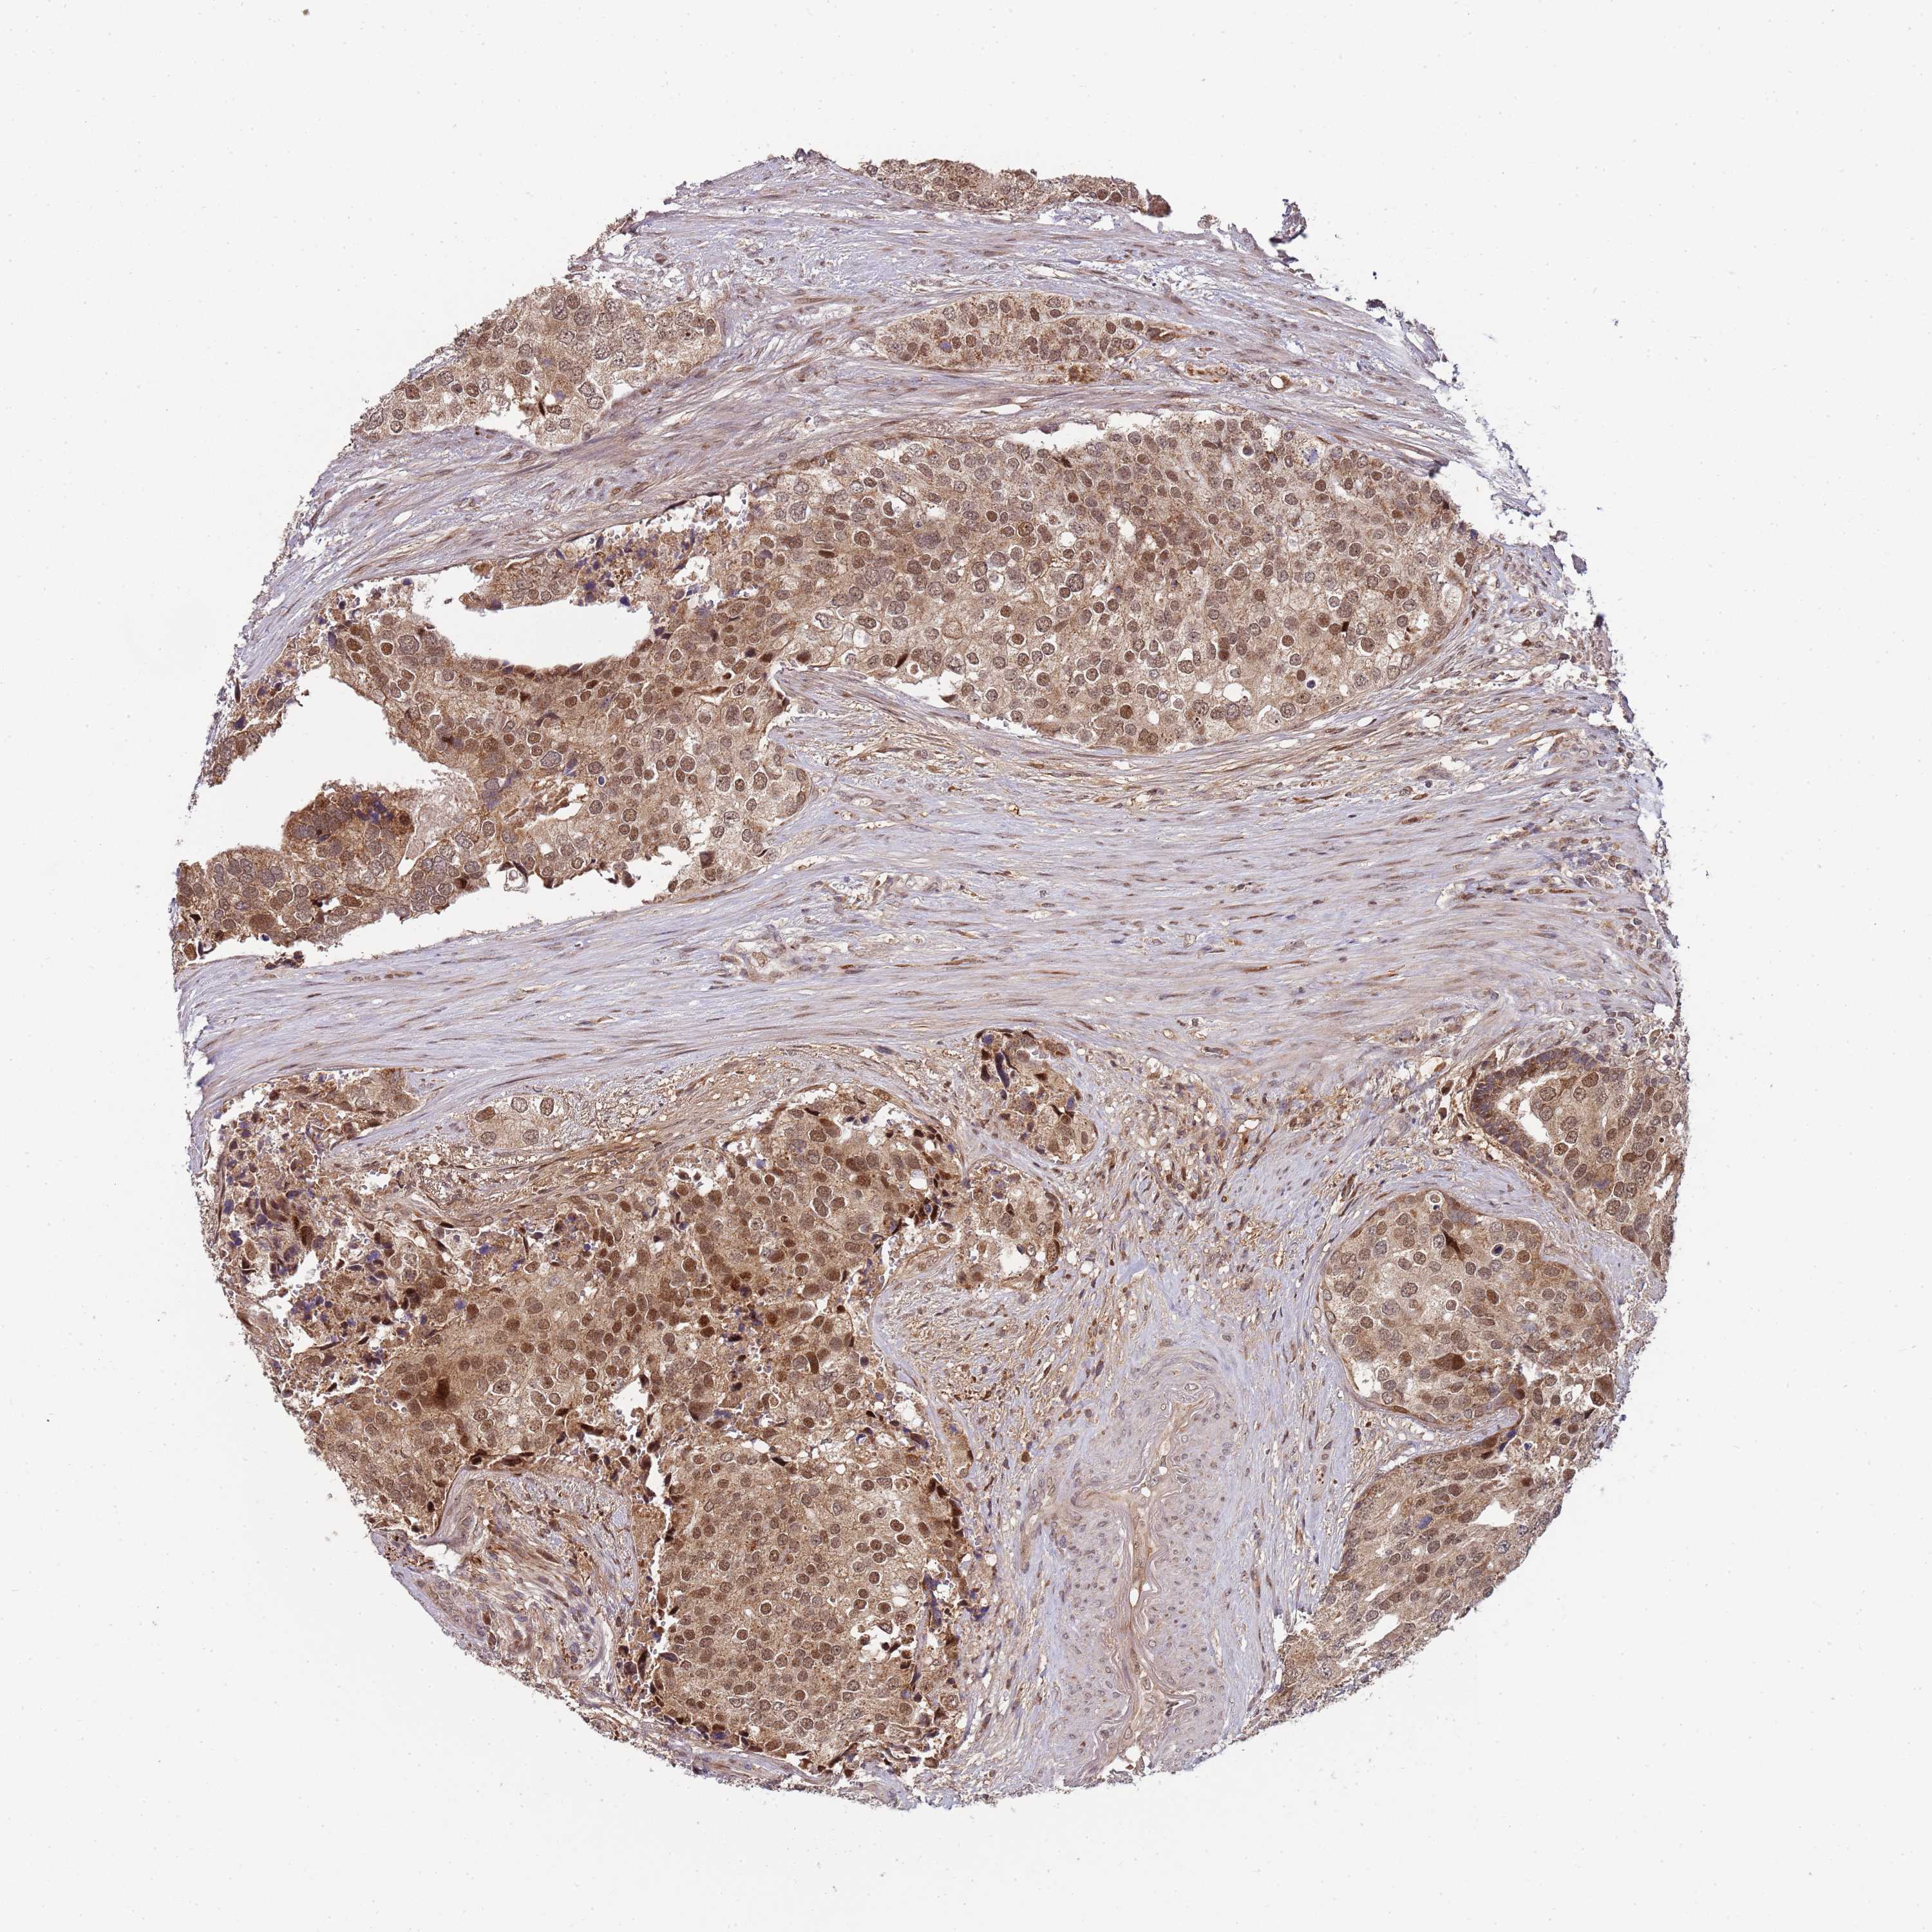

PROSTATE CANCER - Protein expressioni

A mouse-over function shows sample information and annotation data. Click on an image to view it in a full screen mode. Samples can be filtered based on level of antibody staining by selecting one or several of the following categories: high, medium, low and not detected. The assay and annotation is described here.

Note that samples used for immunohistochemistry by the Human Protein Atlas do not correspond to samples in the TCGA dataset.

Antibody stainingi

Antibody staining in the annotated cell types in the current human tissue is reported as not detected, low, medium, or high, based on conventional immunohistochemistry profiling in selected tissues. This score is based on the combination of the staining intensity and fraction of stained cells.

Each image is clickable and will lead to virtual microscopy that enables deeper exploration of all samples and also displays staining intensity scores, fraction scores and subcellular localization as well as patient and tissue information for each sample.

Antibody HPA040650

Antibody HPA044206

Staining

High

Medium

Low

Not detected

Intensity

Strong

Moderate

Weak

Negative

Quantity

>75%

75%-25%

<25%

None

Location

Nuclear

Cytoplasmic/membranous

Cytoplasmic/membranous,nuclear

Adenocarcinoma, NOS

Adenocarcinoma, High grade

Adenocarcinoma, Low grade